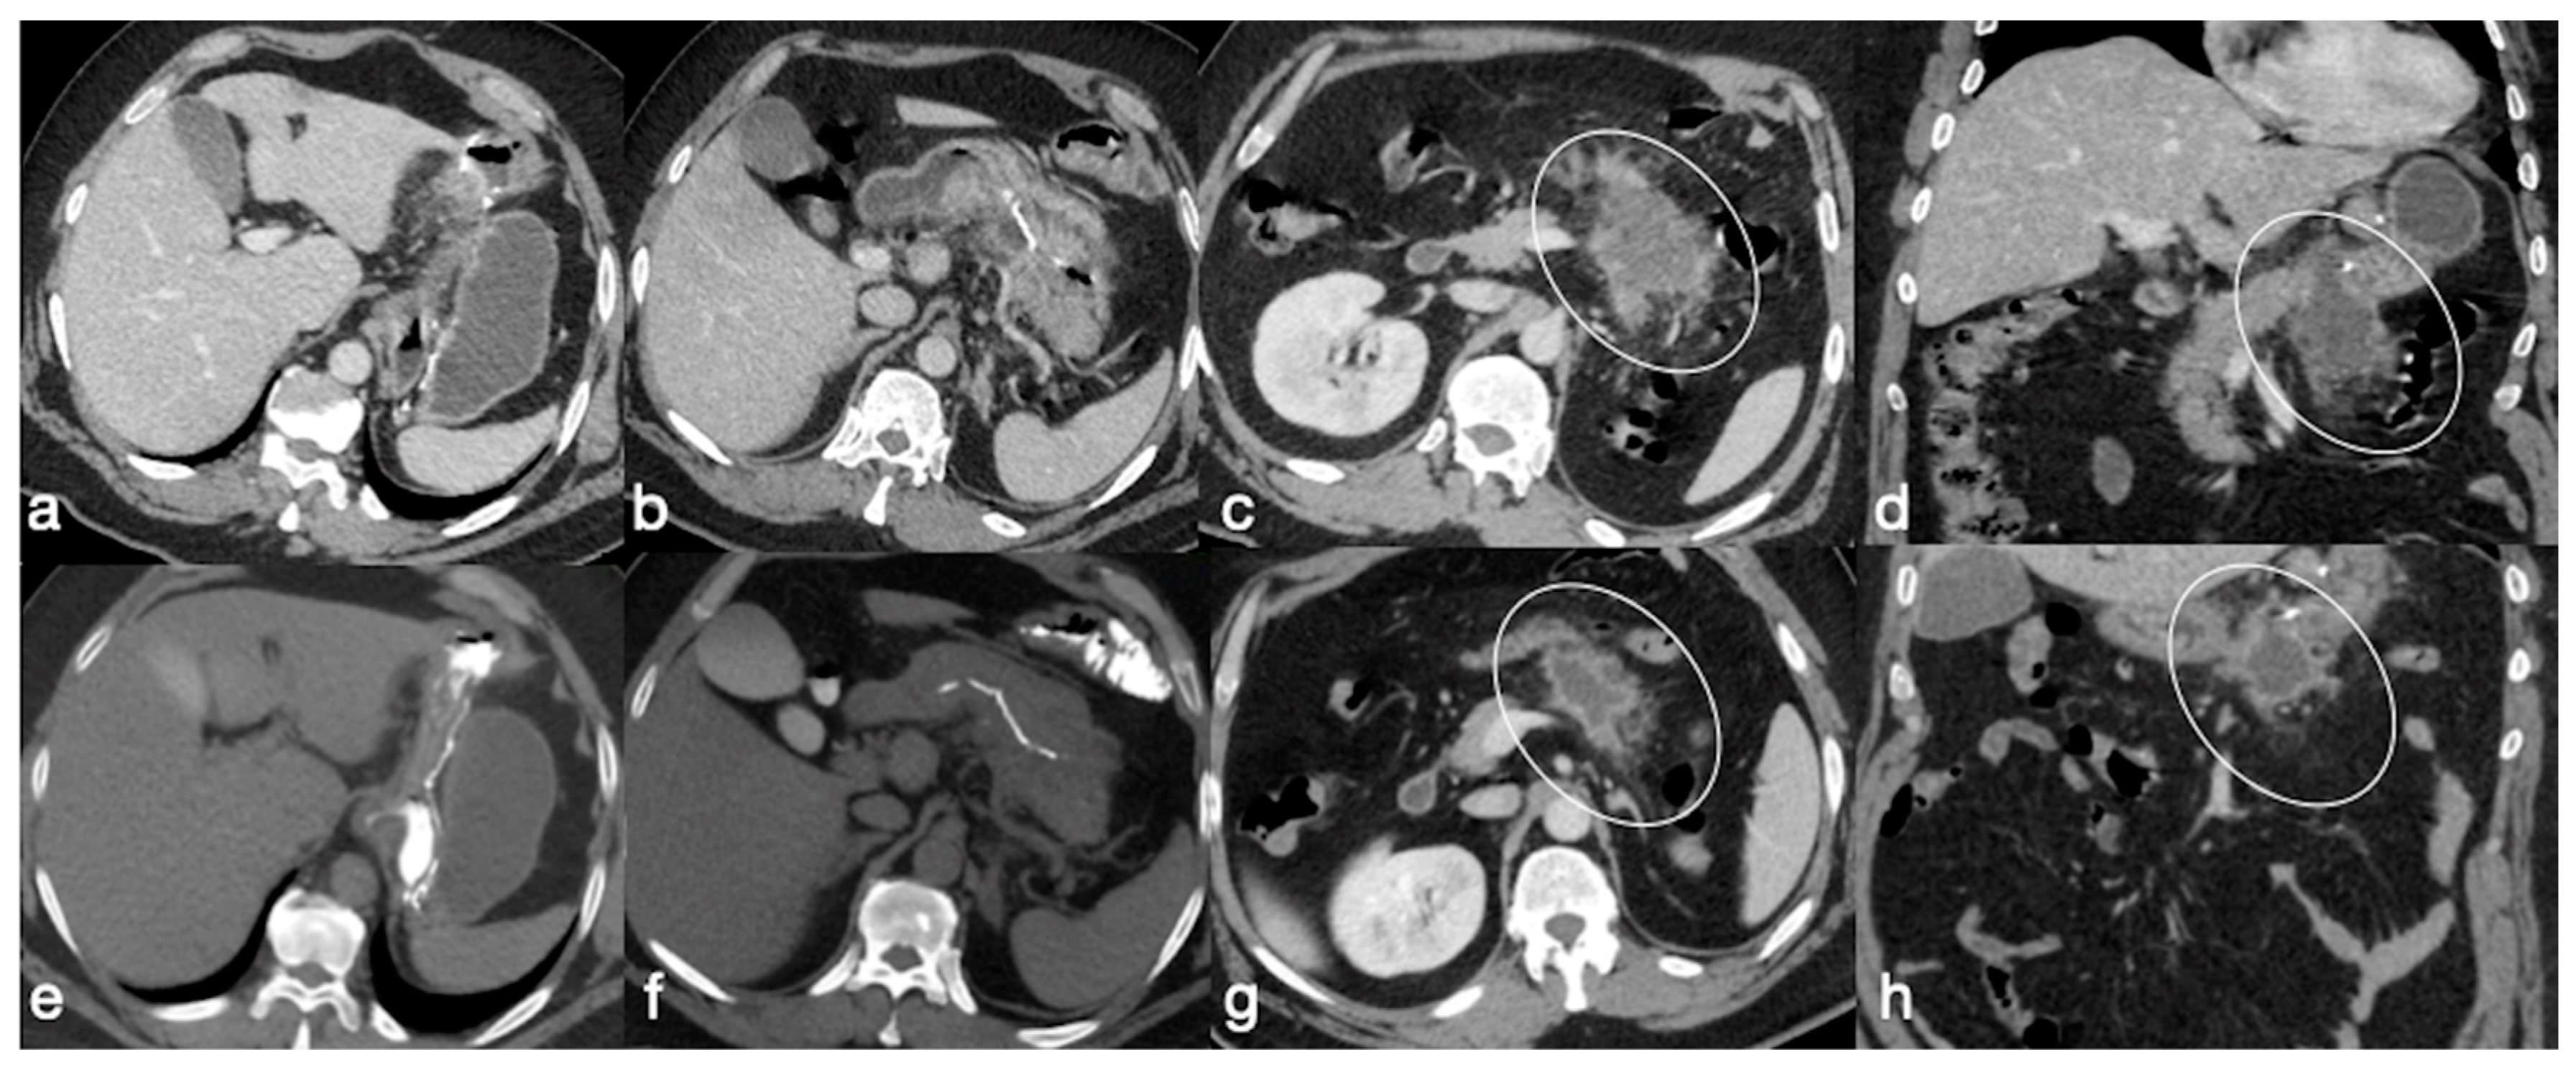

- The obstruction involves the biliopancreatic limb, which appears dilated, whereas the alimentary limb and distal common channel are decompressed. This closed-loop obstruction could determine perforation of excluded gastric cavity. On UGI, there is a dilated and fluid-filled limb (biliopancreatic) excluded by an oral contrast passage that could determine a mass-effect on the other bowel loops. Upon CT, detection is easy, and it should be suspected not only for the biliopancreatic limb appearance associated to decompression of alimentary and common channel, but also for the recognition of dilatation of excluded gastric room.